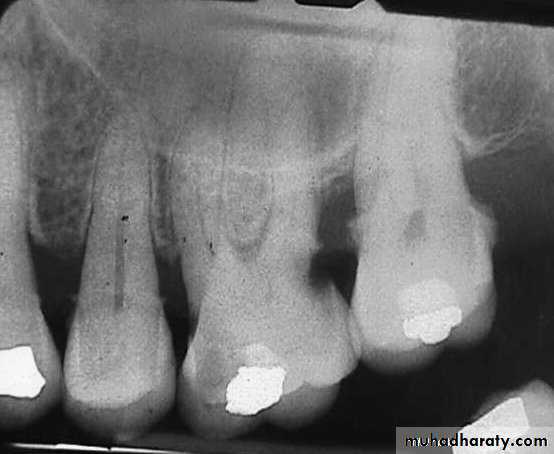

Teeth are composed of pulp (arrow on the secondmolar), enamel (arrow on the first molar), dentin (arrow onthe second premolar), and cementum (usually not visibleradiographically).